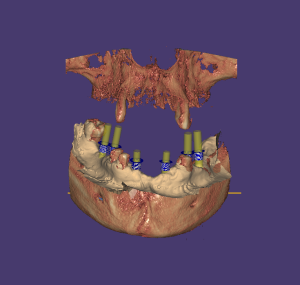

Curso Exoplan BASIC

Carga de la ficha y base de datos (DentalDB)

Manejo del software / Herramientas

Planificación

Guide creator

Curso Exoplan PRO

Curso Exoplan BASIC (Incluido)

Técnica Doble Dicom

Técnica Dicom Stl

Curso Flujo Exocad / Exoplan

Curso integración avanzado para dentistas (incluido)

Curso Exoplan PRO (incluido)

Dirigido a Dentistas los cuales quieran realizar la planificación y diseño del encerado, colocación de implantes Full Mouth y carga inmediata o diferida.